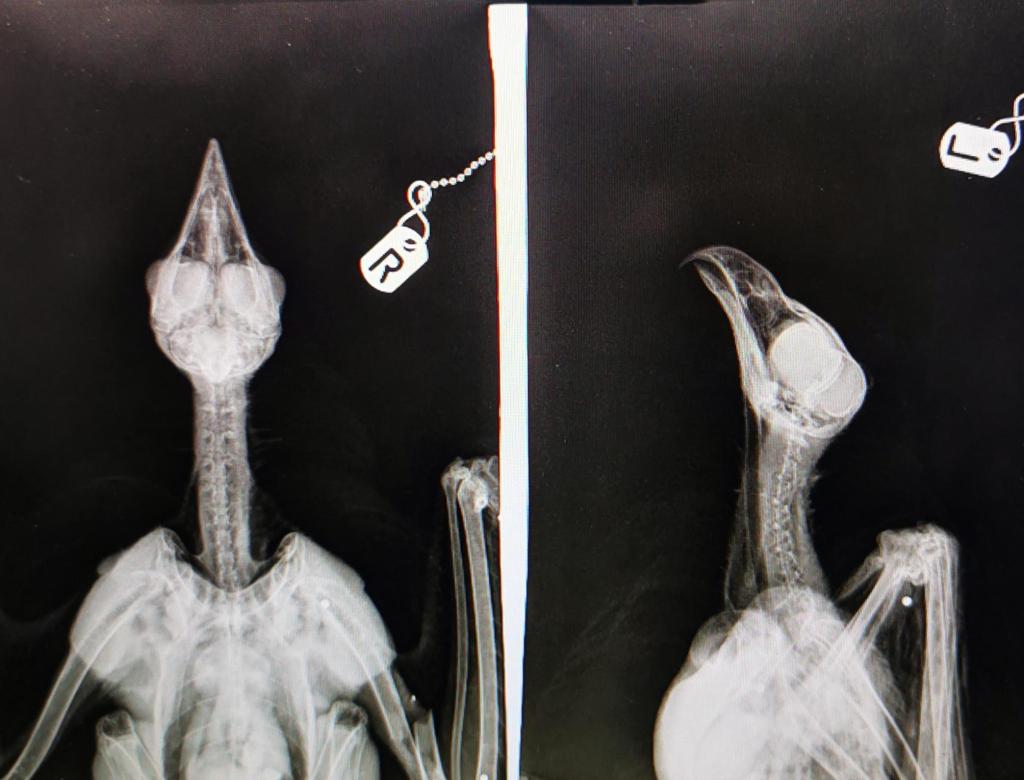

It follows an incident last year when two common buzzards were found dead in Teesdale woodland. Forensic tests indicate they were illegally poisoned with a banned pesticide.

[Two poisoned buzzards. Photo by RSPB]